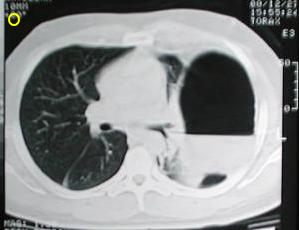

Tomografía Computarizada Tórax

Tomografía de ½ inferior del tórax y abdomen superior con contraste oral, se aprecia desplazamiento del fundus gastrico hacia la base pulmonar izquierda, la grasa epiploica, la brecha diafragmatica, tambien el proyectil y esquirlas metalicas.